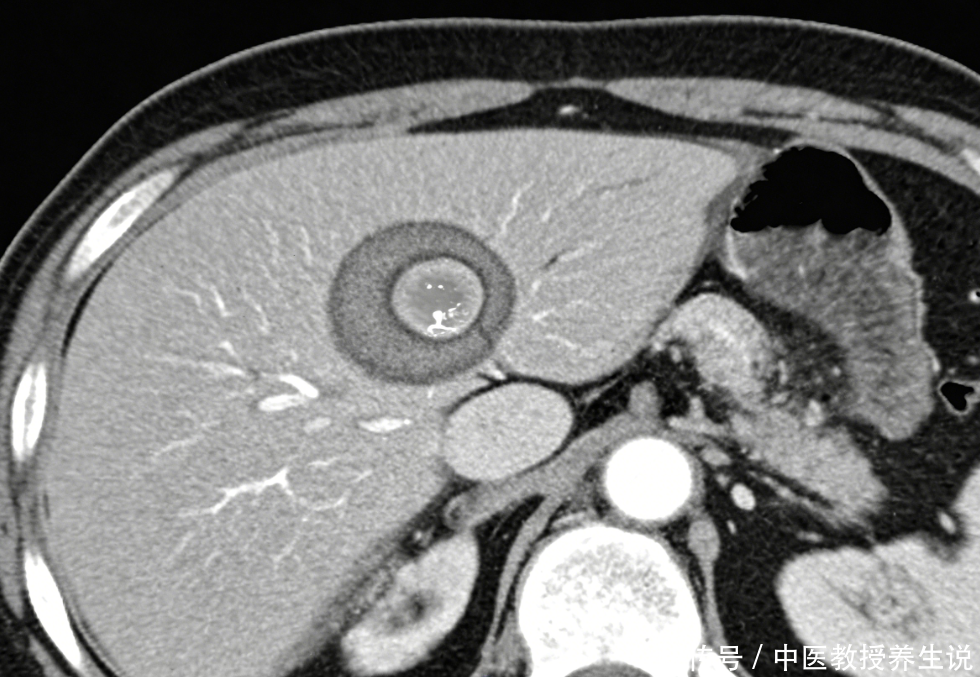

囊肿在好多东谈主的分解里等同于“无害”,但在临床影像学中,它的性质取决于直径、孕育速率以及里面结构。

小于5公分的单纯性囊肿,如实不错暂时和平共处。一朝直径冲突10公分,物理压迫将不行幸免。胃肠谈受压迫会导致餐后饱满、恶心吐逆,这种症状极易被误判为慢性胃炎。若压迫胆管,无痛性黄疸随之而来。

并非通盘囊内王人是澄清的液体。当B超回声自满囊壁增厚、里面出现分隔或实性结节时,这就不是单纯的“水泡”,而是囊腺瘤以致囊腺癌的癌前病变信号。此时的“良性”判断,若莫得增强CT或核磁共振的二次阐发,无异于埋雷。